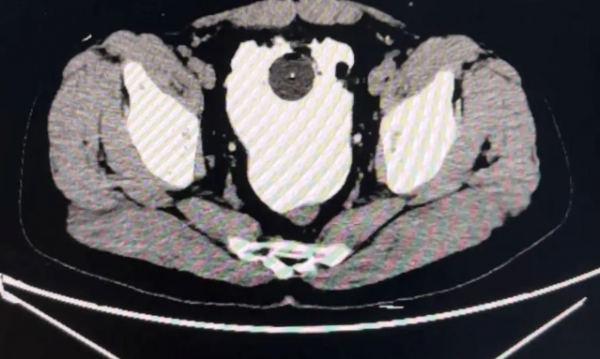

家人发现了男子的异常后,赶紧把他送到了医院,结果医生不检查还好,一检查却发现他的腹腔里有大量的不明积液,这其实都是淡红色的尿液和炎性渗出物。

原来男子因为长时间憋尿,导致膀胱产生了破裂,一个足足有6cm的伤口让他的尿液都进入了腹腔里,而不是排出体外,医生立刻为男子动手术进行治疗。